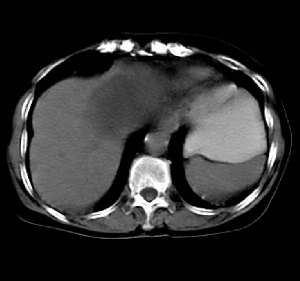

患者无任何不适及阳性体征,超声体检时发现,未做增强扫描。囊影密度均匀,ct值略高于水,囊影壁薄光滑,囊内密度均一。定性诊断不难,应是个囊肿。请大家做个定位诊断

病灶上部层面与肝脏交界清楚但不太截然,下部层面与肝之间可见线状高密度带,考虑由囊块压迫肝实质形成,考虑caroli氏病,其次考虑左肝囊肿向下向肝外生长,另外其他来源囊肿及消化道重复畸形不排除